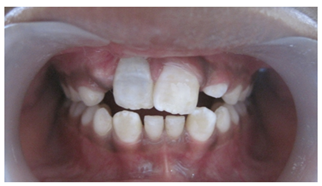

A 10year old boy reported to the department of Pedodontics with a chief complaint of missing upper front tooth and gave a history of fall from bike while 5 days back. They had been to pediatrician for the lacerated lip and got it sutured. Parents had kept the avulsed tooth in paper without knowledge of reimplantation of the same tooth. Patient had no relevant medical and family history. On examination swelling and suture was present on upper lip, lacerated gingiva with healing socket in 11 regions. 21 was intact, vital and non mobile. (Figure 1) (Figure 2) On examination of avulsed tooth 11, it was found to have open apex (Figure 3). On intraoral radiographic examination, no fracture was seen with alveolar bone (Figure 4). Thus avulsed tooth was cleaned and debrided with soft pumice prophylaxis, gentle scaling was done to remove ligament remnants. It was then placed in 1.23% sodium fluoride for 15minutes. Extraoral endodontic therapy was also done using retrograde filling of MTA (Figure 5). Local anesthesia was administered and socket was cleaned, curetted and irrigated to remove clot and debris and 11 was slowly reimplanted in socket. Orthodontic wire – composite splinting was done for 4weeks as the dry storage was more than 60minutes (Figure 6). Systemic antibiotics amoxicillin and doxycycline were prescribed for 5days. The patient was recalled after 1 month and splint was removed. No mobility was present. Again patient was recalled after 2months to check the condition (Figure 7). Again patient was recalled after 6months; tooth had slightly discolored but was not mobile and maintained the space (Figure 8). Patient was happy and contended with the reimplantation of his own tooth without disturbing his original look.

Figure 8Six months postoperative photograph.

Considerable debate exists as to whether it would be beneficial to replant the tooth even though it will inevitably be lost due to resorption. If the patients are followed carefully and if root submerged at the appropriate time, the height and width of the alveolar bone will be maintained allowing for easier permanent restoration at the appropriate time when the facial development of the child is complete.9 A similar case was done, wherein they have reimplanted 7days old maxillary incisor and could successfully achieve the objectives like acceptable esthetics, occlusal function.10 However, in controversy teeth reimplanted after 60mins of dry storage have ankylosed and resorbed within 7years.11 In such cases prosthetic replacement of the missing incisor, space closure with orthodontic treatment or auto transplantation of the premolar together with orthodontic treatment of the malocclusion could have been the treatment options. But in emergency cases orthodontic consultation, prosthetic replacements are seldom possible. Replantation can restore the patient’s esthetic appearance and occlusal function shortly after the injury and the replanted incisor can remain functional for some years.12 Thus in our case we have reimplanted 5days old avulsed maxillary incisor without much complications. Tooth is still intact in place and is serving the purpose. In case of inflammatory root resorption, a new attempt at disinfection of the root canal space by standard retreatment can be considered to reverse the process. Patient is asymptomatic and fully satisfied.